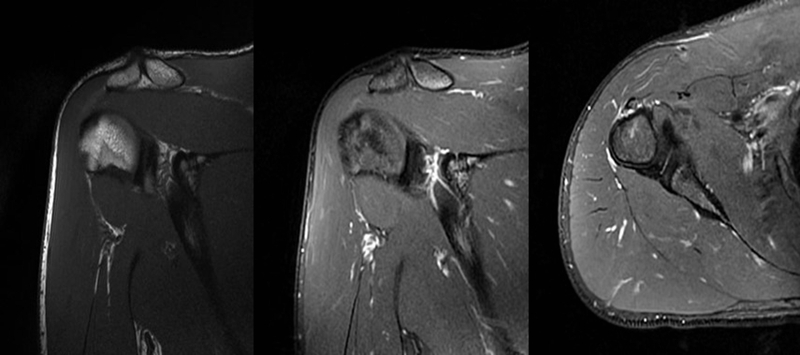

2、MRI检查

MRI目前是诊断肩袖疾病中最常用的检查,可以直观的观察肩袖肌腱。

图17 冈上肌

图18 冈下肌

图19 肩胛下肌

图20 小圆肌

图21 斜冠状位(临床常用)a.T2,b.T1

图22 斜矢状位 a.冈上肌出口,肩袖诊断不如斜冠状位;b.冈上肌及肌腹脂肪浸润成度,评估手术与否

图23 横断位a.正常肩胛下肌;b.肩胛下肌损伤